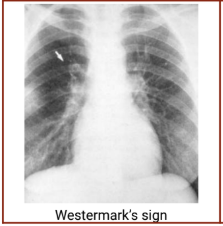

Chest radiography - Westermark’s sign